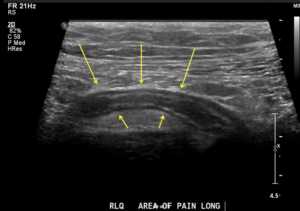

- Диагностирование при помощи аппарата УЗИ. Процедура позволяет без дополнительного проникновения хирургическим путём изучить брюшную полость, рассмотреть, нет ли повреждений внутренних органов. При отсутствии повреждений изучается место бывшего прикрепления отростка слепой кишки. Участок изучается на наличие воспалительного процесса.

Аппендикс на УЗИ